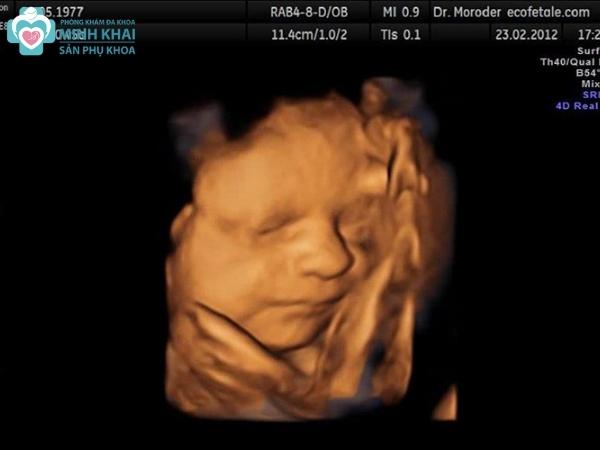

Hình ảnh siêu âm 4D

Hình ảnh siêu âm 4D thể hiện qua ảnh động các chuyển động liên tục của bé con ngay trong thời gian thực khi siêu âm. Thay vì ảnh đen trắng, siêu âm màu 4D cho những hình ảnh có màu sắc với độ phân giải cao và vô cùng chân thực, sắc nét hiển thị rõ trên màn hình. Thêm vào đó, hình ảnh siêu âm 4D còn được máy xử lý tự động cho phép người xem có thể chọn đa dạng các chiều mặt cắt, chế độ xem khác nhau.

Nó có thể chụp lại đầy đủ cấu tạo các bộ phận cơ thể cũng như tái hiện lại các cử chỉ của thai nhi như đạp chân, múa tay, cười,... Chi tiết hơn nữa, kỹ thuật 4D còn giúp quan sát được cấu trúc bộ xương cũng như đa chiều mặt cắt, siêu âm hệ thần kinh, não và tim.